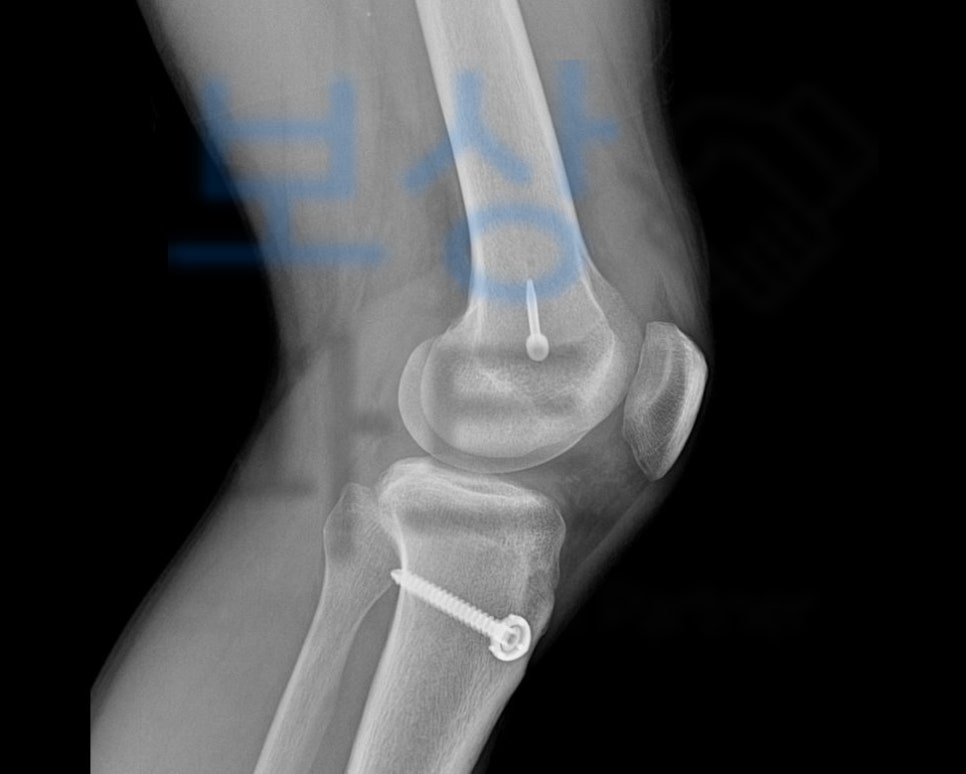

전방십자인대파열로 재건술을 받은 경우 바로 이 무릎의 흔들거림 즉 동요도를 근거로 장해를 평가합니다. 무릎의 동요관절을 평가할 때에는 건측과 환측을 비교하는데요, 바로 이 객관적 검사상 차이나는 동요도로 관절의 기능에 약간, 뚜렷한, 심한 순으로 보험금을 지급하게 되죠.

6mm 이상의 관절 동요로 약간의 장해 5% 지급율에 해당했죠. 저희는 위 후유장애진단서를 기초로 보험금 청구를 진행하였고 적정성을 증명하기 위해 의사자문 및 증빙자료도 함께 송부했습니다.